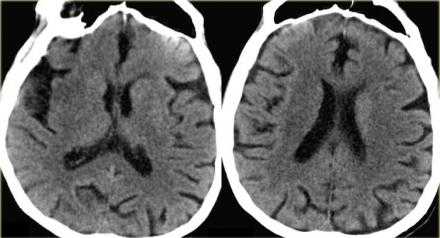

Обратите внимание на изображение и предположите, где патология. После продолжите чтение. Вывод:

Есть некоторая гиподенсность и отек в левой лобной доли со старостью борозд в сравнении с контр-латеральной стороной. Далее DWI снимки того же пациента. После просмотра DWI нет сомнения, что это инфаркт. Именно поэтому DWI называют инсульт последовательностью.